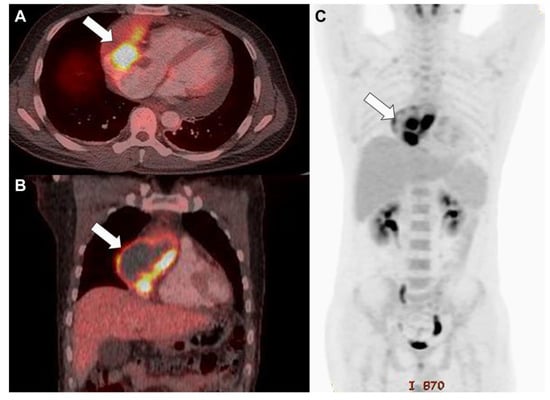

Figure 3. Fluorodeoxyglucose-positron emission tomography/computed tomography indicated increased uptake in the mass (white arrow) and a hypointense region filled with fluid in the axial (A) and coronal sections (B) and direct invasion into the great vessels without evidence of distant metastasis (C).

Diagnostics 13 02666 g003